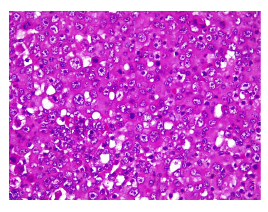

Al hacer una nueva revisión de todo el material de histopatología y los estudios de inmunohistoquímica, se reportaron resultados negativos para HMB45, CD30, CD5, HLA-DR, CD43, CD87, CD7, CD4, CD2, CD1A, melan-A, CD45, CD20, ALK1, p63, PAX5, CD3, CD56, GATA3, andrógenos y PLQ, y positivos para EMA, CK, SOX10, CK7 y S100, por lo que se consideró que se trataba de un adenocarcinoma apocrino de glándula sudorípara primario axilar (figuras 5-8).

Histológicamente, el tumor está conformado por células epiteliales con abundante citoplasma granular eosinófilo, parcialmente vacuolado. Puede tener diferenciación ductal y secreción por decapitación. El pleomorfismo y las figuras mitóticas son variables. El nucléolo tiende a ser conspicuo. En algunas ocasiones puede adoptar patrones morfológicos con células en anillo de sello o aspecto histiocitoide, similar al carcinoma de células en anillo de sello o histiocitoide periorbitario. En la inmunohistoquímica, las células tumorales son positivas para citoqueratina 7 y tienen expresión variable para CEA, S100, EMA, estrógenos y progesterona 12. Anticuerpos como el EKH5 y el EKH6 son específicos para los órganos con secreción ecrina y han demostrado ser útiles 5. Otros criterios para el diagnóstico histológico incluyen material positivo para PAS y resistente a la diastasa en células luminales, positividad inmunohistoquímica para GCDFP-15 6, así como expresión positiva para el receptor de andrógenos.